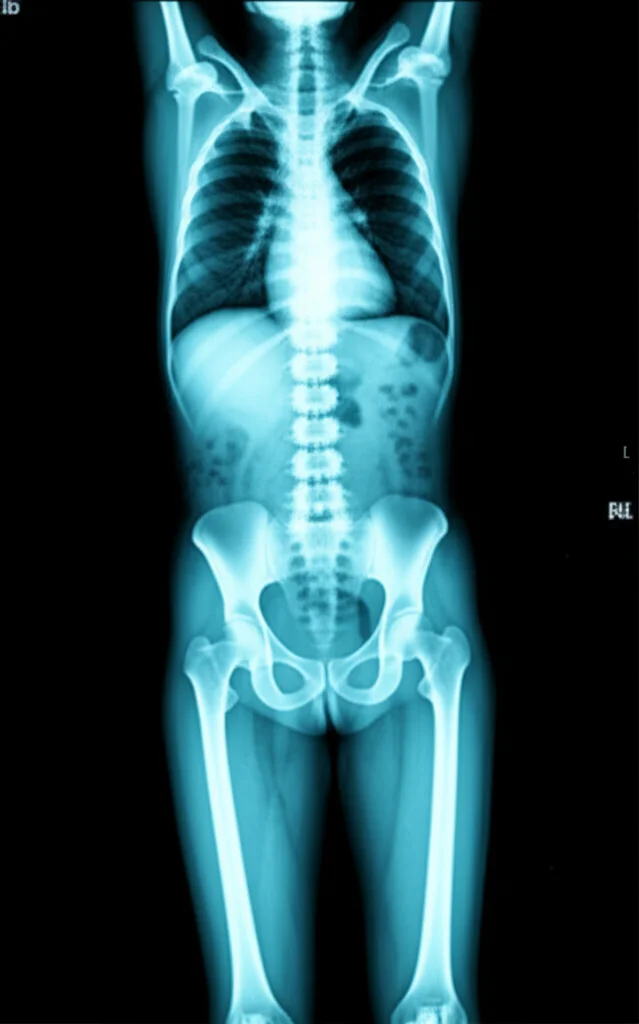

Un Ritorno al Futuro: La Scintigrafia Ossea Scheletrica

E se la soluzione fosse qualcosa di già noto, ma forse un po’ dimenticato per questa specifica indicazione? Sto parlando della scintigrafia ossea scheletrica total body trifasica. Già negli anni ’90, alcuni studi pionieristici avevano suggerito il suo potenziale: Spitz e colleghi, nel 1992, riportavano che in circa un quarto dei pazienti politraumatizzati esaminati con scintigrafia si trovavano fratture aggiuntive. Addirittura, proponevano di inserirla nella routine diagnostica, un po’ come si fa per la stadiazione dei tumori. Altri, come Runkel nel 1993, confermavano questi dati, trovando ben 68 fratture in più in 53 pazienti. Nonostante l’alta sensibilità e la bassa esposizione alle radiazioni, la scintigrafia non ha mai veramente preso piede come esame di routine in questo contesto. Un vero peccato, secondo me.

Perché la Scintigrafia Vede di Più?

Vi chiederete come mai la TAC, considerata il gold standard, si perda così tanti pezzi. Beh, ci sono delle spiegazioni. Ad esempio, le fratture costali sono spesso difficili da vedere sulla TAC politrauma perché i tagli assiali non sono sempre ortogonali alle coste. Anche per le estremità ci sono dei “punti ciechi”: gli arti superiori, posizionati sull’addome durante la scansione, possono generare artefatti e la regione del carpo può non essere visualizzata con la giusta angolazione. Per gli arti inferiori, la scansione si ferma spesso al bacino, a meno che non ci siano sospetti specifici, quindi lesioni più distali possono sfuggire. La scintigrafia, invece, “fotografa” l’attività metabolica dell’osso, evidenziando le aree di rimaneggiamento tipiche di una frattura, anche quelle più piccole o in posizioni difficili.

Certo, anche la scintigrafia non è infallibile al 100%. Nel nostro studio, 3 fratture non sono state rilevate (due metacarpali mascherate da fratture del carpo e una della scapola, forse per una localizzazione troppo vicina al tronco e una scintigrafia un po’ precoce). E in 25 casi ha dato un “falso allarme”, poi rivelatosi legato a cambiamenti degenerativi. Ma la sua specificità è comunque rimasta altissima (99.4%), di poco inferiore a quella della diagnostica di sala traumi (99.9%).